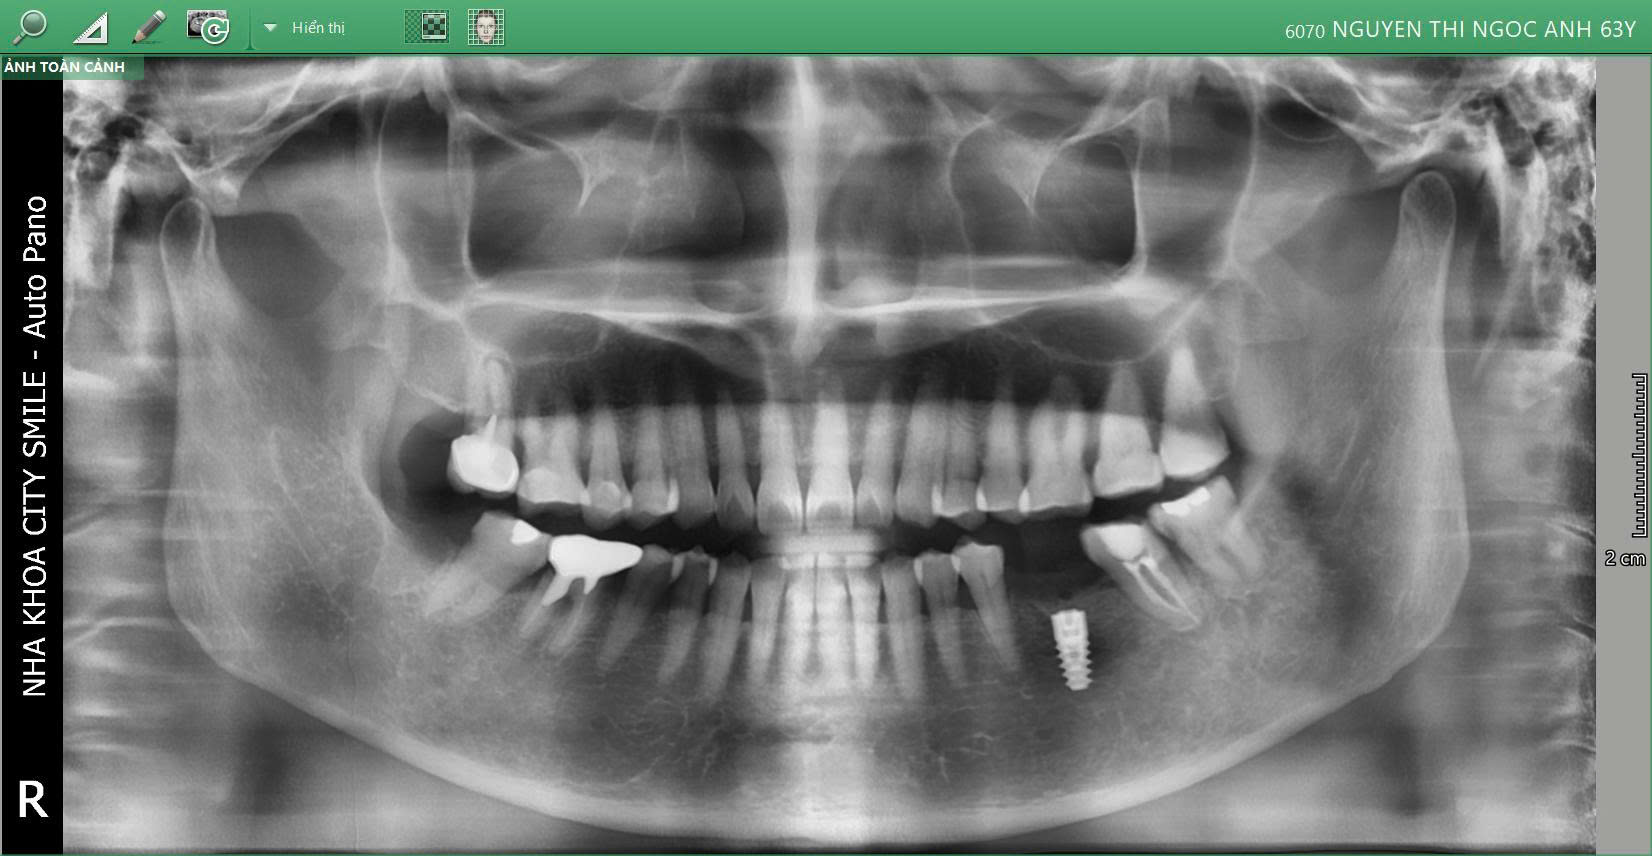

3. Kết quả điều trị

Sau khi thực hiện, cô Ánh không còn hiện tượng đau nhức răng khôn, ăn uống dễ dàng hơn.

Vùng Implant tích hợp tốt, chuẩn bị cho giai đoạn phục hình răng sứ, giúp khôi phục chức năng ăn nhai bền vững và thẩm mỹ tự nhiên.